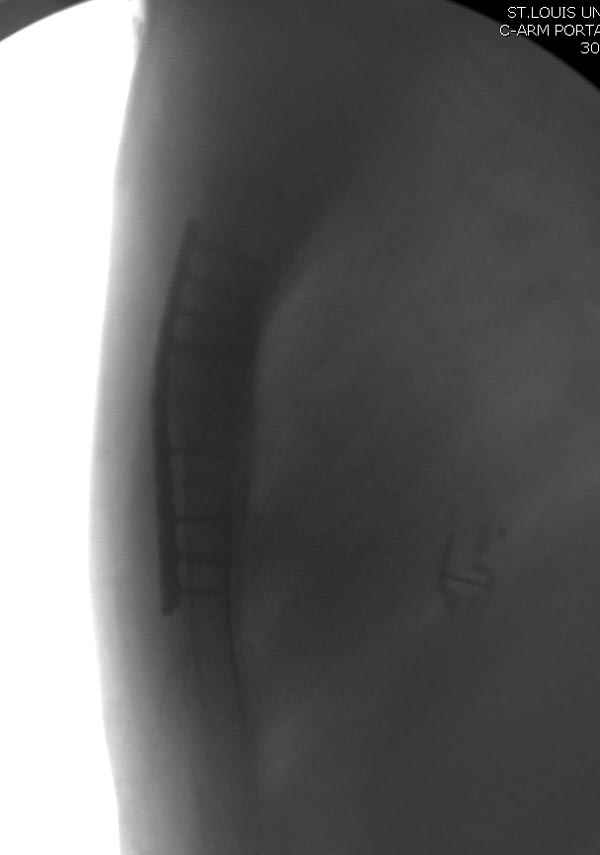

Ложный сустав зафиксирован двумя пластинами 2.4 мм (locking plate) позаимствованными из челюстно-лицевой хирургии, с костной пластикой, все остальные пластины мне показались слишком толстыми, грубые для грудины или отсутсвовали возможности создания угловой стабильности.

Рентген снимки во время операции и последние сделаны на днях.